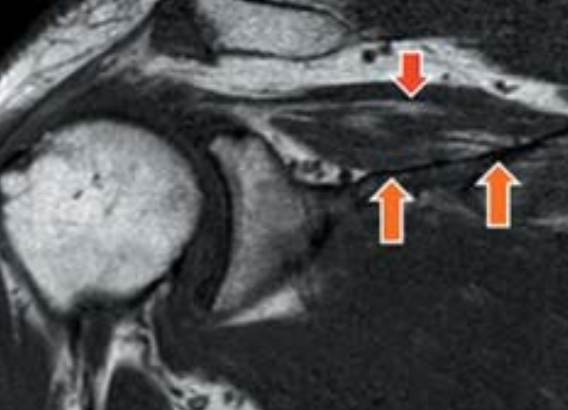

脂肪変性とは、腱板損傷をおこした筋肉内に起こる変化です。腱板損傷によって機能の低下した筋肉内に脂肪細胞が浸潤することで脂肪変性が発生します。

脂肪変性を併発しているということは、腱板筋の弾力性や機能が低下していることの証左になるので、腱板再建術を施行しても再断裂する可能性が高くなります。

腱板再建術後の再断裂を予測する目的で、GoutallierらはCT画像を使用して脂肪変性を5段階に分類しました。今では、CTよりもMRIの分類に置き換わっています。

腱板損傷後の脂肪変性併発率は30~70%とバラツキがあり、腱板損傷後3ヵ月以降に画像上で認められることが多くなります。